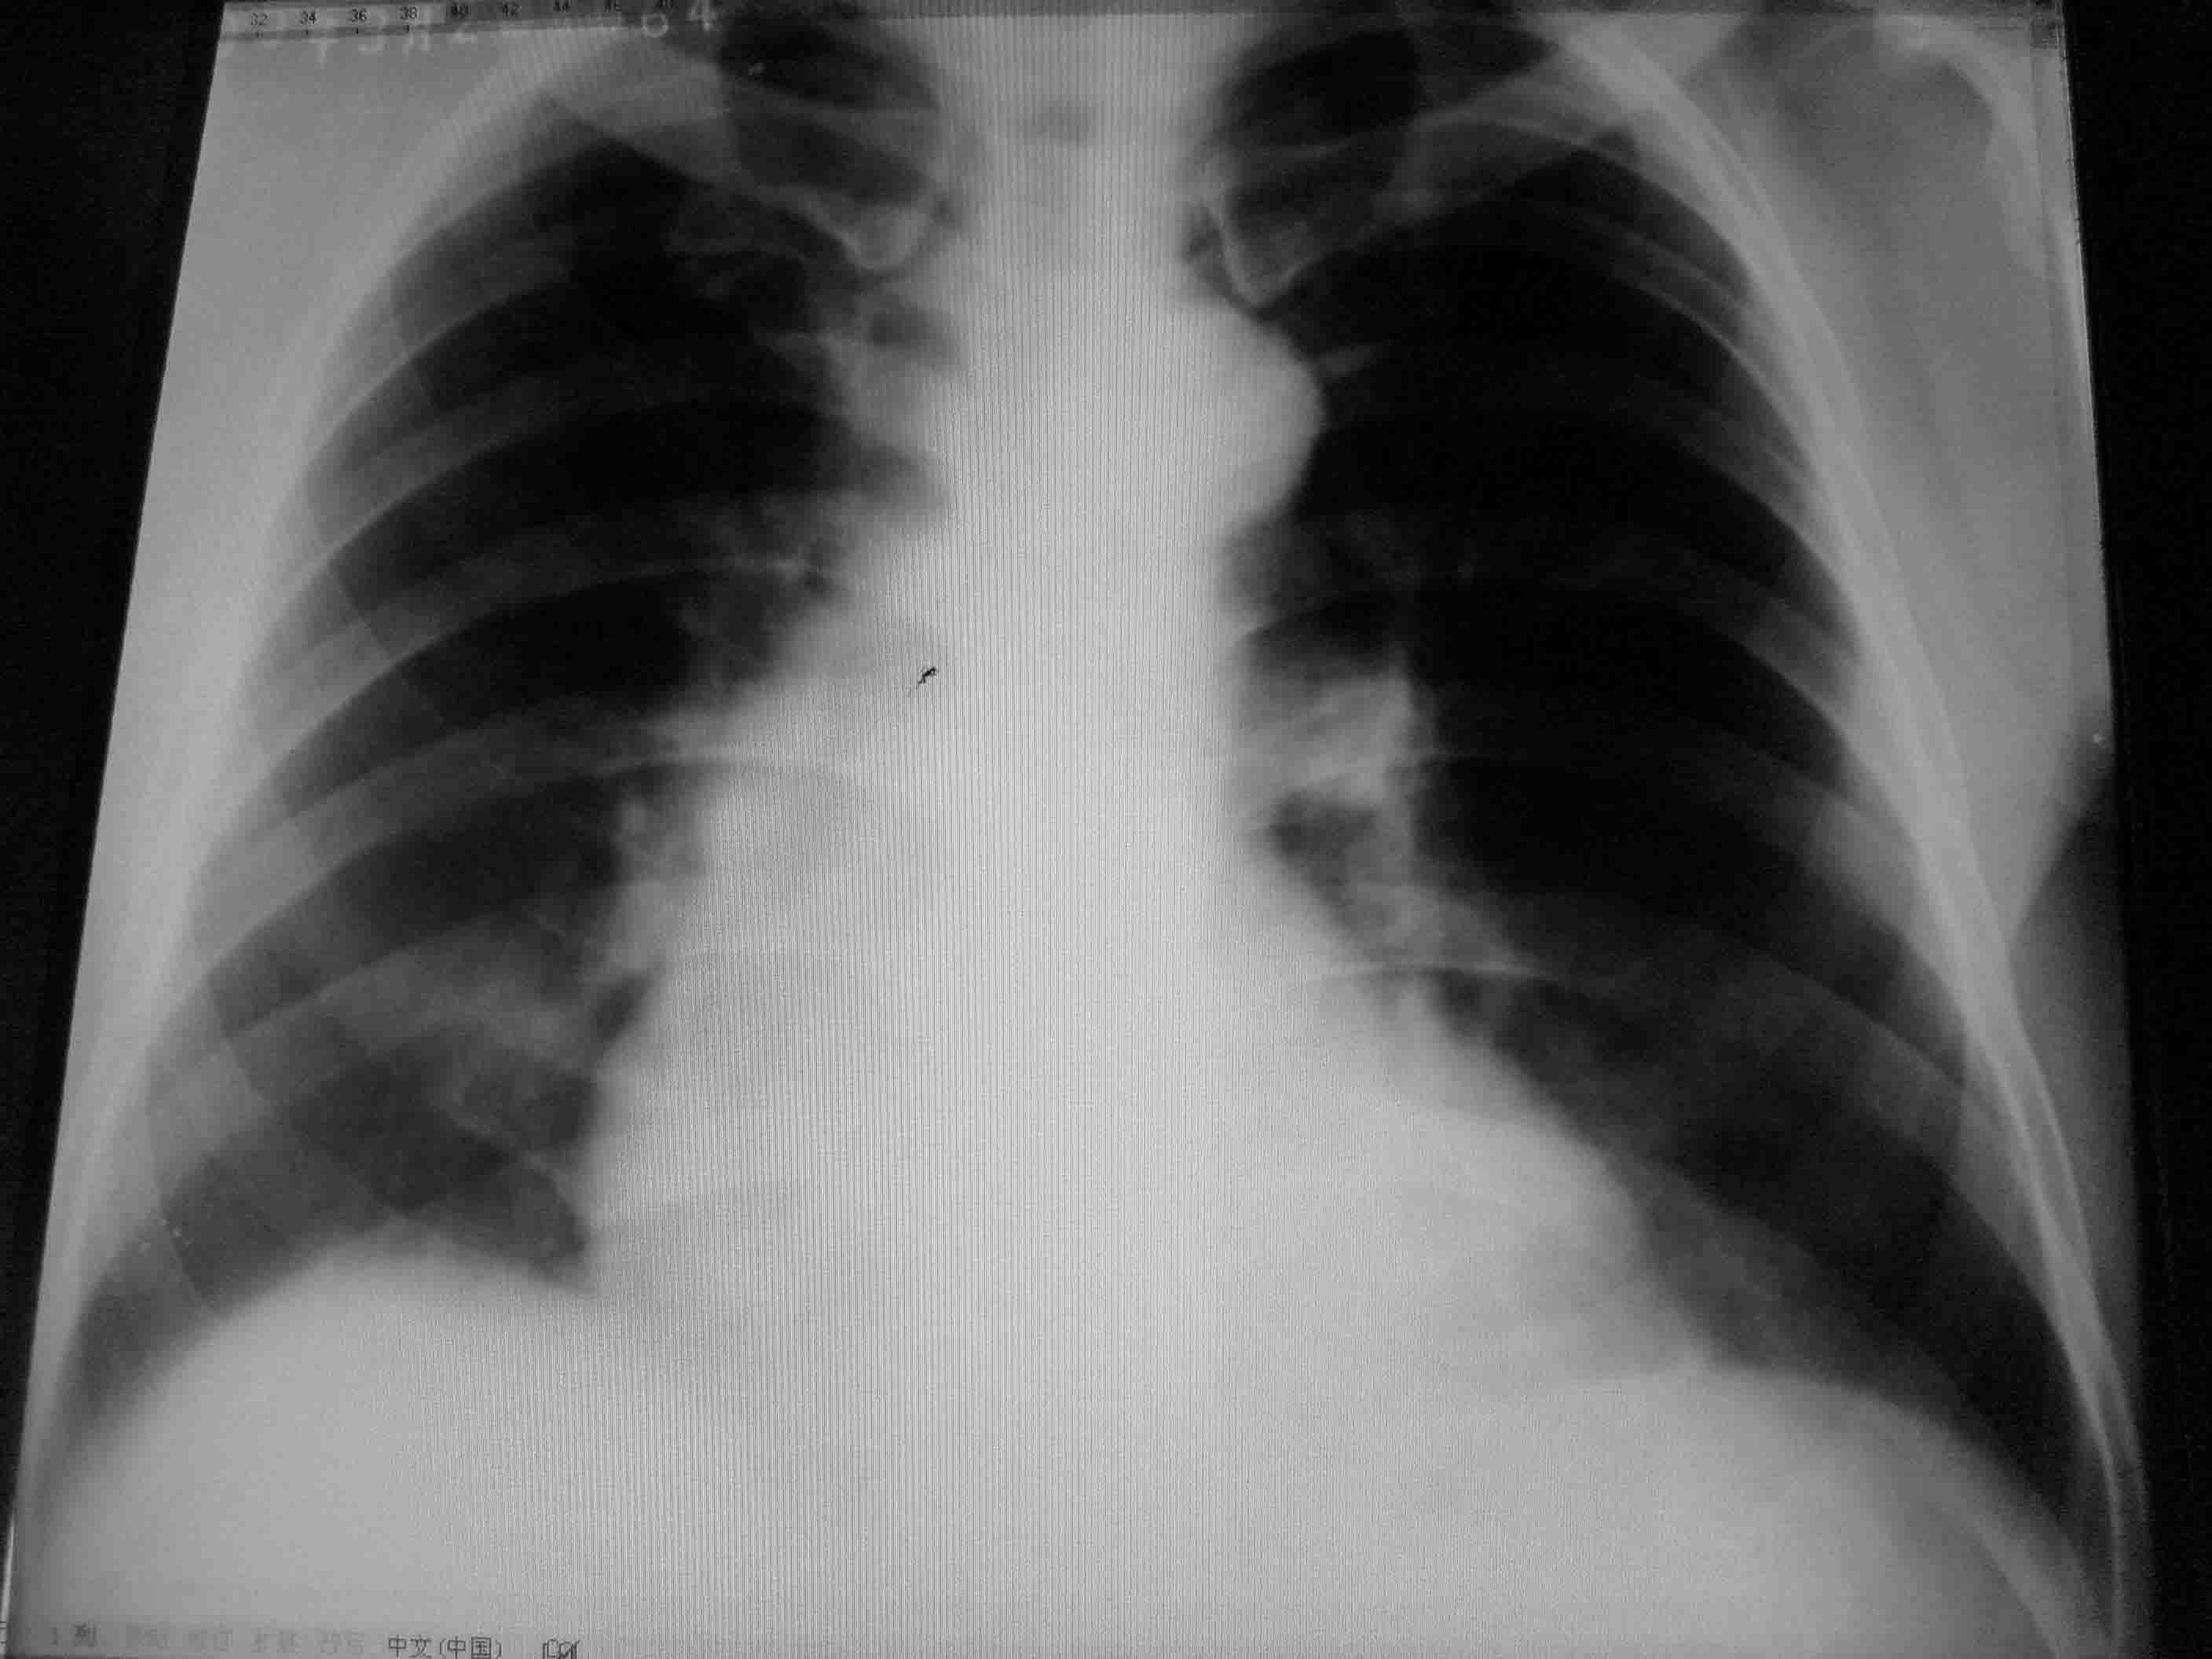

患者,男、61岁,肺部感染治疗后复查,

本片显示右下肺野淡薄片状阴影,主动脉型心影外形,左心膈角区可能是心包脂肪垫影。既然是肺部感染复查,最好是原片、片查片一起上,好作为一个比较。

片子应该是好片子,分析可能是翻拍时心脏透亮位置反光造成的伪影。